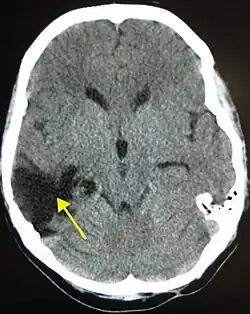

| CT scan showing cerebral contusions, hemorrhage within the hemispheres, and subdural hematoma. There is also displaced skull fracture of left transverse parietal and temporal bones.[2] | |

One type of focal injury, cerebral laceration, occurs when the tissue is cut or torn.[37] Such tearing is common in orbitofrontal cortex in particular, because of bony protrusions on the interior skull ridge above the eyes.[31] In a similar injury, cerebral contusion (bruising of brain tissue), blood is mixed among tissue.[23] In contrast, intracranial hemorrhage involves bleeding that is not mixed with tissue.[37]

Hematomas, also focal lesions, are collections of blood in or around the brain that can result from hemorrhage.[11] Intracerebral hemorrhage, with bleeding in the brain tissue itself, is an intra-axial lesion. Extra-axial lesions include epidural hematoma, subdural hematoma, subarachnoid hemorrhage, and intraventricular hemorrhage.[38] Epidural hematoma involves bleeding into the area between the skull and the dura mater, the outermost of the three membranes surrounding the brain.[11] In subdural hematoma, bleeding occurs between the dura and the arachnoid mater.[23] Subarachnoid hemorrhage involves bleeding into the space between the arachnoid membrane and the pia mater.[23] Intraventricular hemorrhage occurs when there is bleeding in the ventricles.[38]

The preferred radiologic test in the emergency setting to determine the severity of a TBI is computed tomography (CT): it is quick, accurate, and widely available.[80] Follow-up CT scans may be performed later to determine whether the injury has progressed.[10]